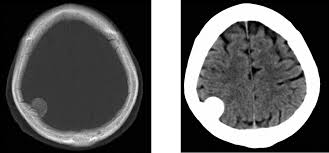

Frecuencia y resultados clínicos asociados con la positividad cerebral de tau en la tomografía por emisión de positrones

19 junio 2025

En un estudio observacional de gran tamaño se observó que la tasa de PET cerebral positivo para tau alcanzaba un 10%  en individuos sin deterioro cognitivo, y la combinación de positividad para PET de amiloide beta (Aβ) y tau se asoció con un alto riesgo de progresión clínica, tanto en la etapa preclínica como en la sintomática de la enfermedad de Alzheimer. Estos hallazgos subrayan el potencial de la PET para tau como biomarcador para la estadificación de la enfermedad. JAMA, 16 de junio de 2025.